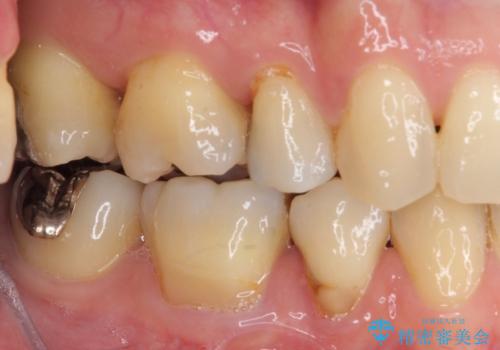

- 上下前歯の叢生を気にして来院された患者様です。

費用を抑え、期間もあまりかけずに治療をしたいとのことで、インビザライン・ライトを用いて矯正治療を行うこととしました。

矯正治療後には、下顎臼歯の目立つ銀歯をセラミックインレーにて修復治療を行いました。

インビザライン・ライトは、製作できるアライナーの枚数に制限があるため、移動可能な量に限りがあります。

軽微な後戻りの治療であったため、十分に治療を行うことができました。

口を開けたときに金属が見えなくなり、患者様には大変満足していただきました。